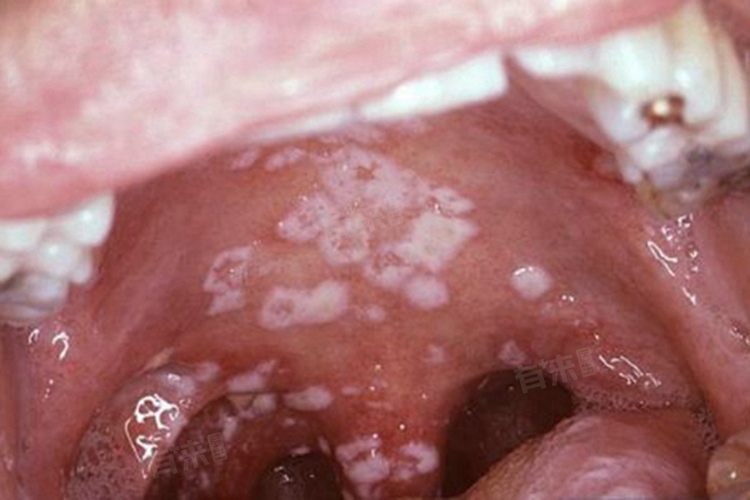

口腔黏膜白斑病是一种常见的口腔黏膜疾病,表现为口腔黏膜上出现白色斑块,且不能被擦掉,也无法诊断为其他已知疾病。其发病是多种局部和外部因素共同作用的结果,这些因素干扰了口腔黏膜细胞的正常代谢和分化,最终导致白斑形成,如吸烟、局部刺激等。

- 念珠菌是常见的口腔条件致病性真菌,当口腔内环境改变,如长期使用抗生素、免疫功能下降时,念珠菌大量繁殖引发感染。念珠菌感染破坏口腔黏膜防御屏障,导致黏膜细胞代谢紊乱,诱发白斑。临床上,部分口腔黏膜白斑病患者病损部位可检测到念珠菌。

- 是常见的口腔黏膜慢性炎症性疾病,可表现为口腔黏膜出现白色条纹、斑块等病损,其病因尚不明确,可能与免疫、遗传、感染等多种因素有关。扁平苔藓的白色斑块与口腔黏膜白斑病有时难以区分,病理检查可见上皮基底细胞液化变性,固有层有淋巴细胞浸润带,且有一定恶变倾向。